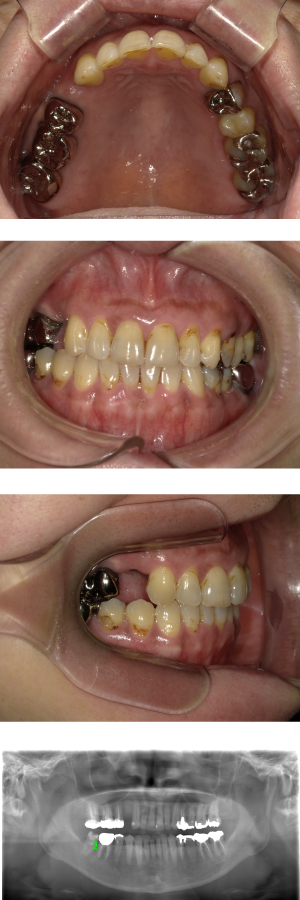

インプラント治療(左上5ソケット・GBR 右上2左上13GBR)

| 年代・性別 | 50代・男性 |

| 主訴 | 入れ歯だと咬めなくてつらい。 |

| 部位 | 上顎②1①2③4⑤Br |

| 治療期間 | 約9ヶ月 |

| 費用 | ¥1,794,100(税込) |

| 副作用・リスク |

|